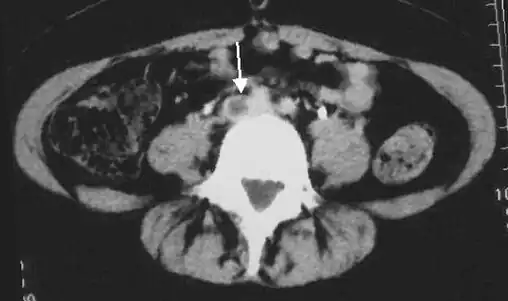

-

An ultrasound with a blood clot visible in the left common femoral vein. (The common femoral vein is distal to the external iliac vein.)

An abdominal CT scan demonstrating an iliofemoral DVT, with the clot in the right common iliac vein of the pelvis